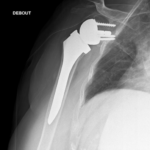

Le but de la prothèse de l’épaule est d’enlever les zones d’os et de cartilage qui sont usées, et de les remplacer par des pièces artificielles ayant les mêmes formes.